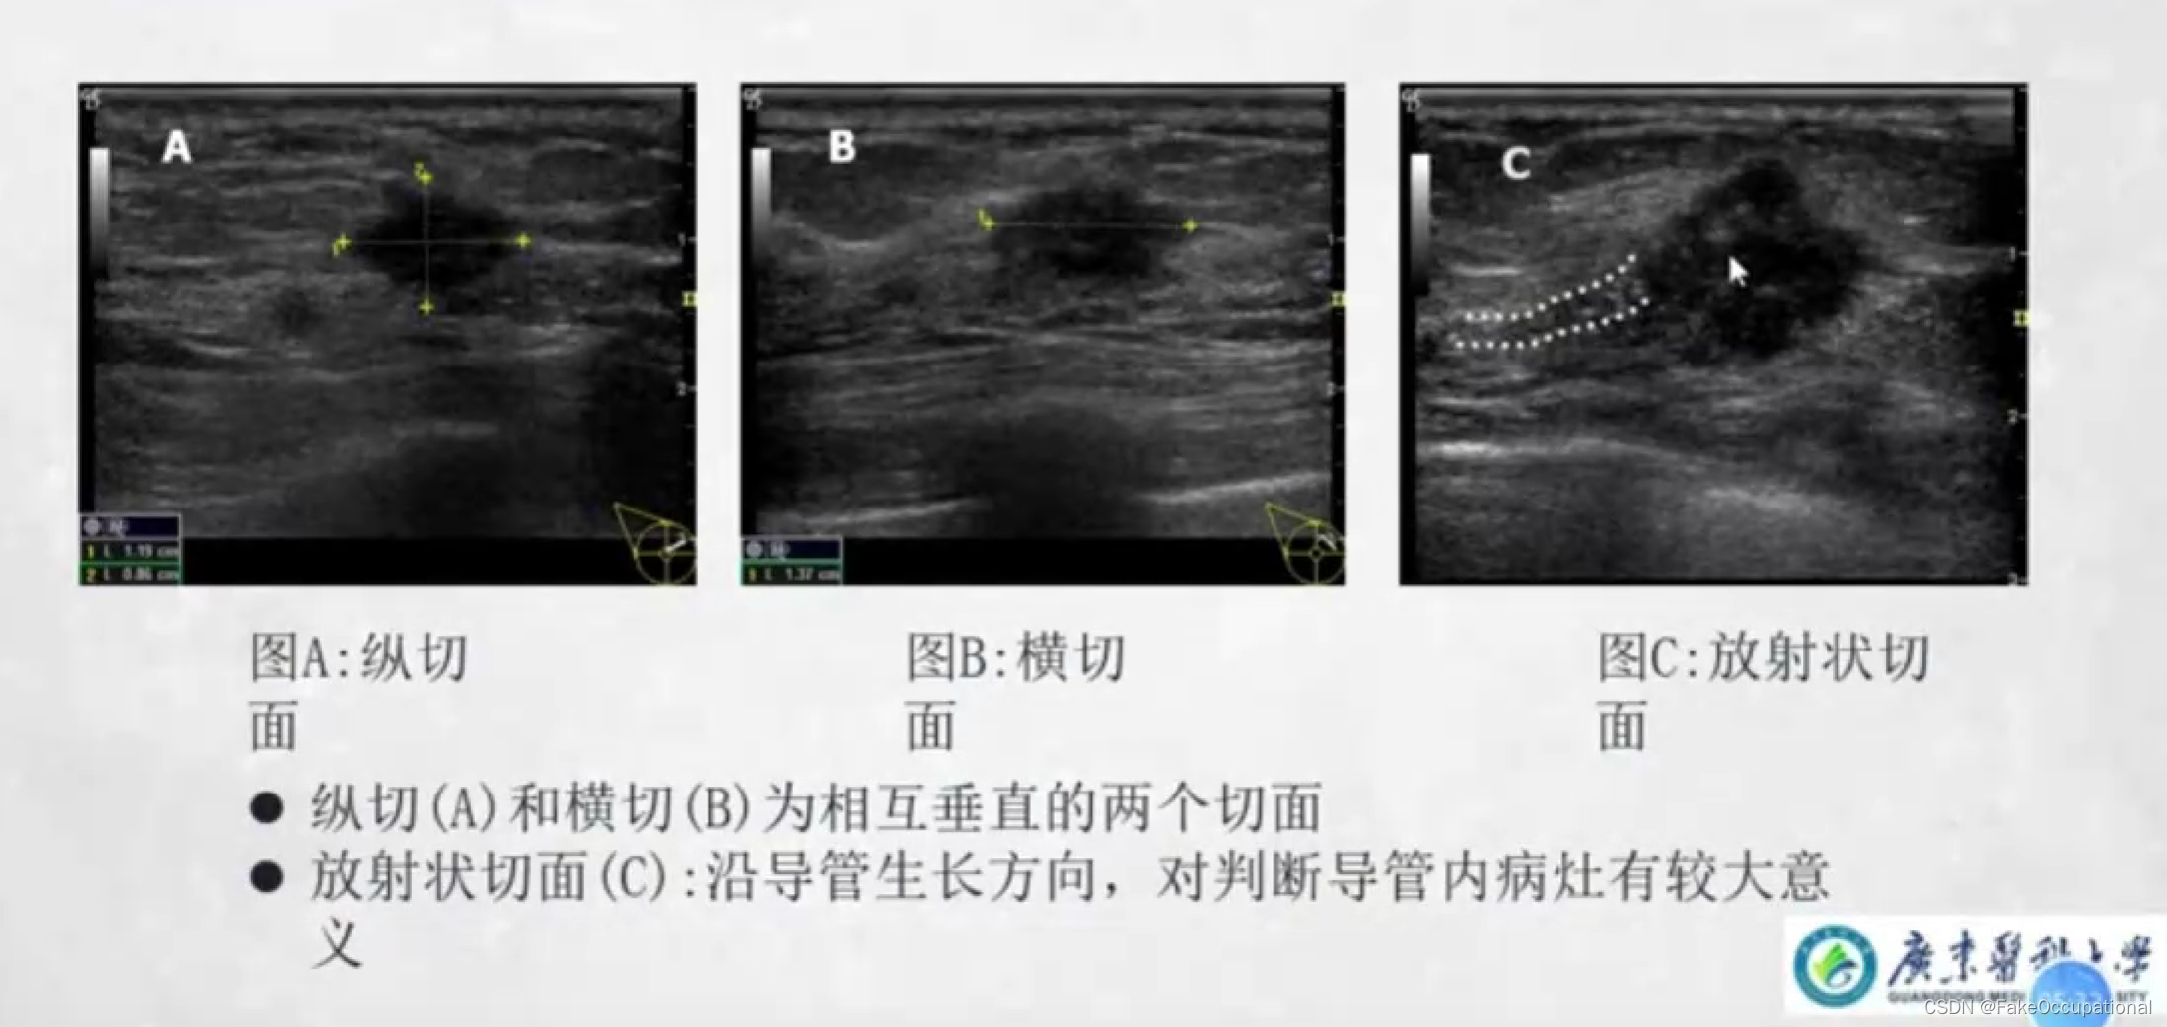

乳腺超声检查技术

- 全面扫查: 乳头后区域适当斜切,必要时可增加耦合剂